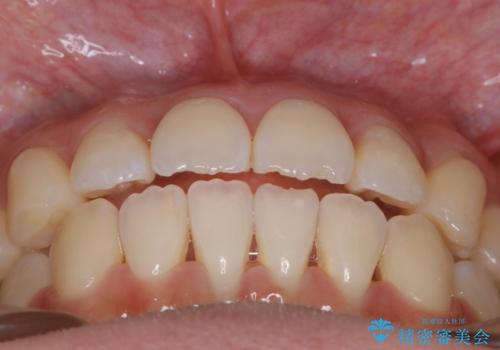

- 上下の歯のガタつきを主訴にご来院されました。

前歯部に特にガタつきが見られ、正中もズレている状態でした。

矯正装置の希望がインビザラインだったため、マイクロインプラントを併用し、奥歯から順に遠心移動をかけていくことにより非抜歯でも主訴のガタつきを治すことができました。

術前・術後の笑った時の歯の見え方の変化にも注目してみてください!